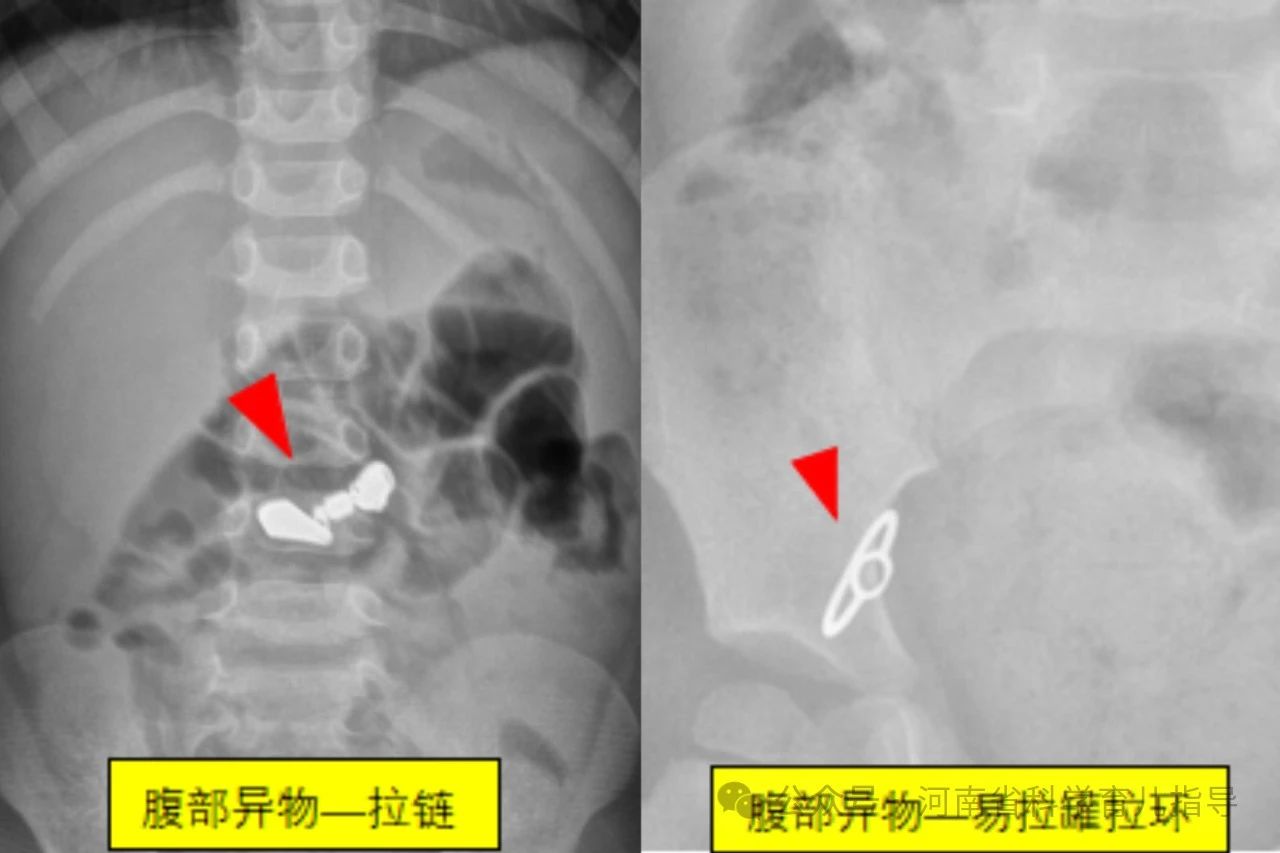

消化道异物儿童消化道异物是指儿童误吞了不能被消化且未及时排出而滞留在消化道的各种物体,文献中已报道的有硬币、果核、碎骨、电池、磁性异物、玩具、指甲、乳牙、笔头、塑料笔帽、电动牙刷头、大头针、戒指、图钉、螺丝钉、别针、纽扣、毛发等等。根据其形状主要包括以下几种,圆钝型异物如硬币,钢珠,螺丝帽,电池,棋子等圆形或者边缘比较平钝、光滑的物体,扁平状或球型。尖锐型异物如针状,钉状或者钩状物体,还有不规则型异物如女性的金属饰品发卡,生活用品如温度计中的水银等。其中形状不规则或者尖锐异物、纽扣电池、多枚磁性异物或单枚磁性异物合并金属异物发生并发症的风险较高,危险性较大。

经搜集我们郑州大学第三附属医院医学影像科最近7年间的图像存储系统的X线报告,查找可疑小儿消化道异物的病例541例,即家长发现家中某些东西不见了,但未直接看见或不确定孩子是否吞咽异物。通过X线拍片检查确认存在消化道异物病例共338例,阳性病例约62.5%。338例消化道异物中硬币183例,磁力珠15例,电池20例,水银22例,磁铁3例,钢针7例,钢珠10例,钉类14例,围棋子7例,其他个别如发卡,手链,钥匙,戒指,果核,易拉罐环,子弹头,纽扣,拉链等少数。发生消化道异物的小儿年龄最小的3个月,最大的6岁。23例在1岁以内,且多数在6个月到1岁之间;1岁74例,2岁94例,3岁77例,4岁43例,5岁24例,6岁3例。由此可以看出小儿发生消化道异物的年龄大多数在1~5岁之间,当然1岁以下甚至3个月的小婴儿也可以发生,这需要家长朋友们特别注意。

圆钝型异物形态规则,边缘比较光滑,短时间不会对身体造成伤害。较大的异物可能会卡在消化道生理性狭窄的部位,如口咽部,食道或胃窦幽门部等引起不适或者机械性梗阻,需要请专业医生借助专用器械取出。较小的异物一般情况下容易通过消化道自然排泄出来,家长朋友们无需过多担心和焦虑,根据孩子的大便习惯,观察确认异物排出即可。但纽扣电池存在腐蚀性化学成分,会对存留部位造成腐蚀伤,不同时间吞咽多个磁力珠会因其磁力相互吸引对肠道进行挤压造成肠道缺血坏死,最好能及时发现,尽早取出,减少伤害。